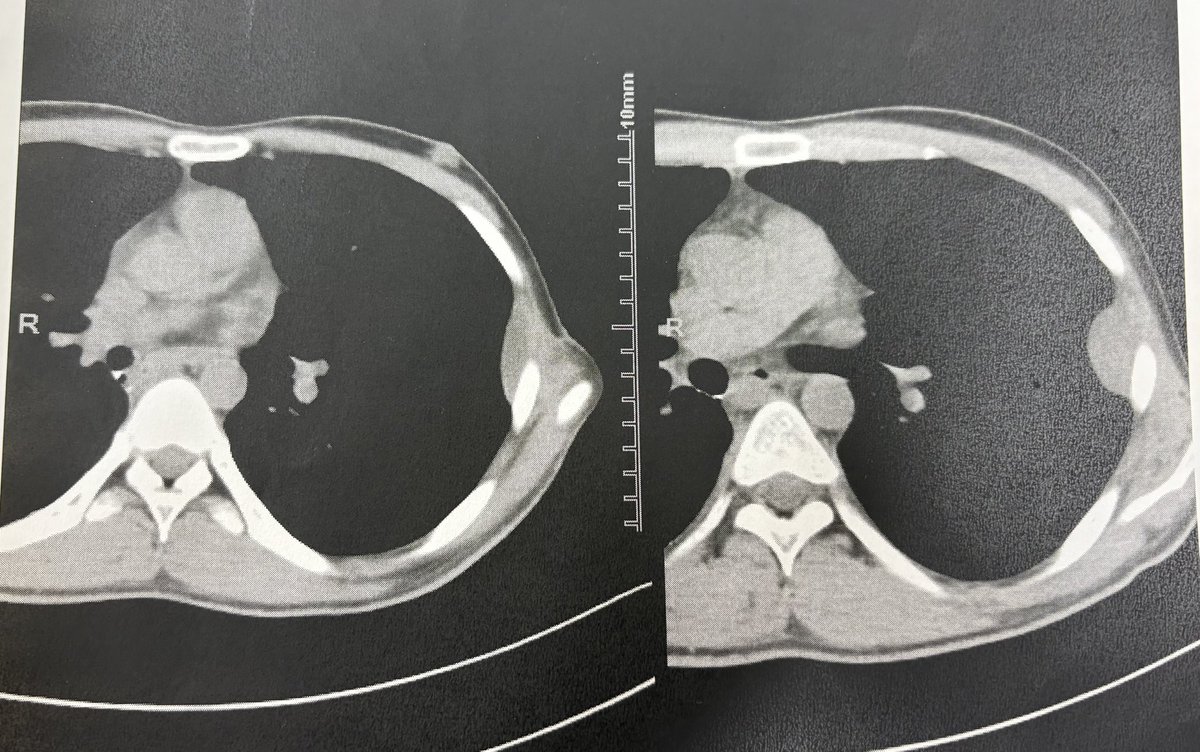

2023/3月から2024/2月まで化学療法効かなくてイフォマイドもしました。化学療法が効きにくい軟骨肉腫と判明 25回の手術現在21歳 #骨肉腫 #癌 #片足 Instagram⬇️